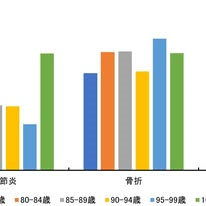

ある市町村の後期高齢者の関節炎,骨折(主に転倒で発生),骨関連疾患の医療費.骨折から要介護につながる.中長期的な予防が最も重要です!

ある市町村の後期高齢者の関節炎,骨折(主に転倒で発生),骨関連疾患の医療費.骨折から要介護につながる.中長期的な予防が最も重要です!